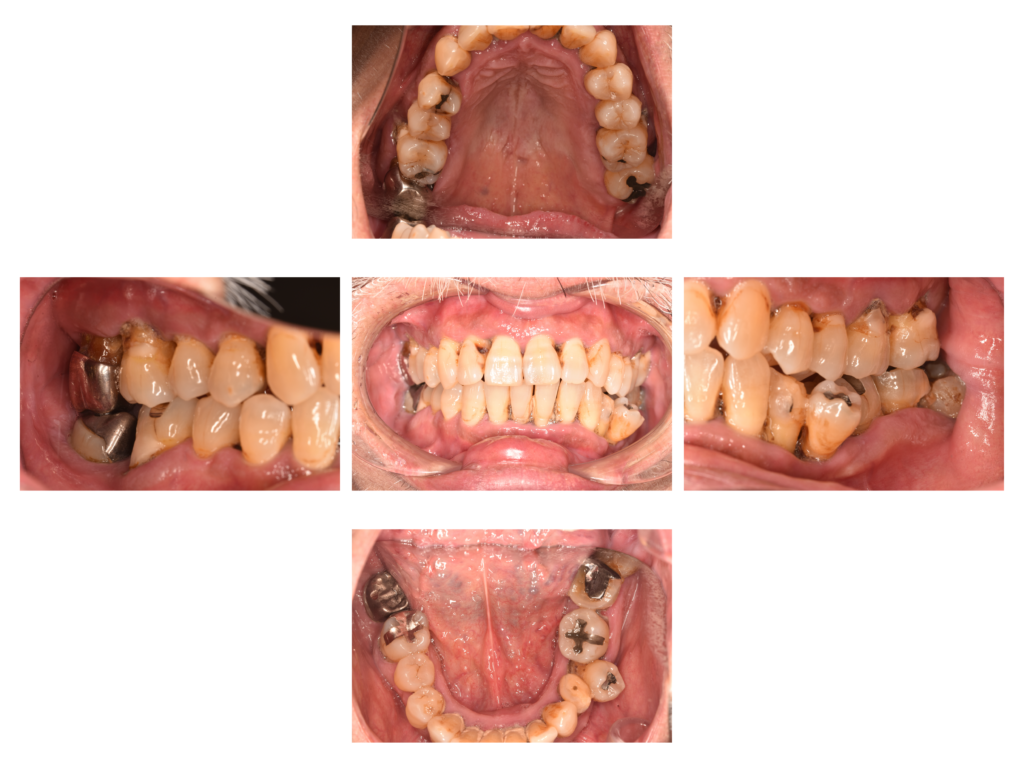

患者さんは下の前歯が揺れることを主訴に来院されました。家族から口臭も指摘されていたそうです。

歯磨きはしっかりされているそうですが、歯肉付近のブラッシングが不十分で歯石が多くの部位に沈着していました。

歯間ブラシから治療を始めています。ひたすら歯間ブラシの指導とSRPをおこなっています。

歯間ブラシはLION DENT.EX 3Sサイズから初めて、徐々に歯間ブラシのサイズを上げていきます。

重度歯周病の部位が多数あり、歯周病により根管治療(神経の治療)が必要な歯も複数あったので、その治療も同時におこなっています。

↑現在は歯磨きの状態が改善し、綺麗で引き締まったピンクの歯肉が維持されています。顕著な歯肉の退縮を全体的に認めますが、このまま経過を見続けます。今でこの歯肉退縮ですから、臼歯(奥歯)の歯周外科治療をするともっと歯肉が下がってしまいます。